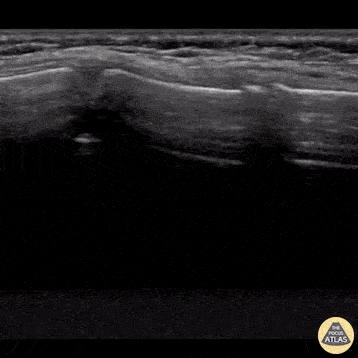

8 year old male presented following blunt thoracic trauma from having fallen out of a bouncy house. Clinically he had reproducible bony tenderness to palpation of the anterior chest wall. POCUS revealed normal lung slide in the setting of a sternal fracture. The fracture is pictured on the left side of the image as a defect in the cortex with adjacent swelling/hematoma formation; also notice a buckle fracture to the sternal growth plate at the right of the screen. Dr. Paul Khalil, Emergency Medicine Physician @denverem